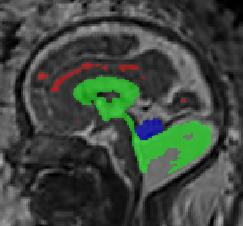

Limiting failures of machine learning systems is of paramount importance for safety-critical applications. In order to improve the robustness of machine learning systems, Distributionally Robust Optimization (DRO) has been proposed as a generalization of Empirical Risk Minimization (ERM). However, its use in deep learning has been severely restricted due to the relative inefficiency of the optimizers available for DRO in comparison to the wide-spread variants of Stochastic Gradient Descent (SGD) optimizers for ERM. We propose SGD with hardness weighted sampling, a principled and efficient optimization method for DRO in machine learning that is particularly suited in the context of deep learning. Similar to a hard example mining strategy in practice, the proposed algorithm is straightforward to implement and computationally as efficient as SGD-based optimizers used for deep learning, requiring minimal overhead computation. In contrast to typical ad hoc hard mining approaches, we prove the convergence of our DRO algorithm for over-parameterized deep learning networks with ReLU activation and a finite number of layers and parameters. Our experiments on fetal brain 3D MRI segmentation and brain tumor segmentation in MRI demonstrate the feasibility and the usefulness of our approach. Using our hardness weighted sampling for training a state-of-the-art deep learning pipeline leads to improved robustness to anatomical variabilities in automatic fetal brain 3D MRI segmentation using deep learning and to improved robustness to the image protocol variations in brain tumor segmentation. Our code is available at https://github.com/LucasFidon/HardnessWeightedSampler.